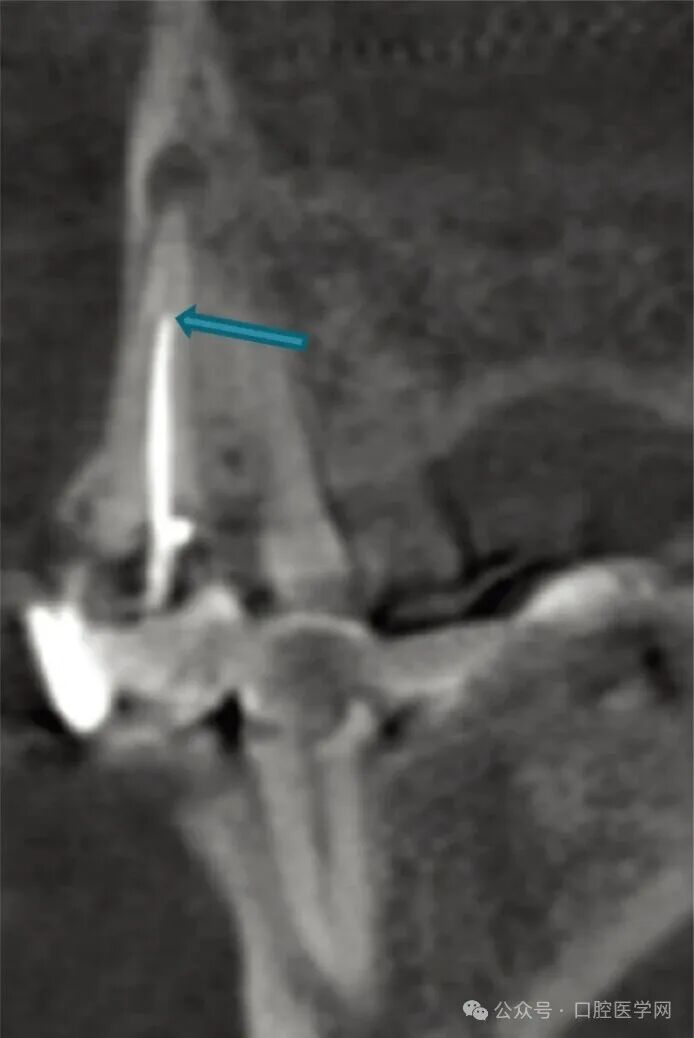

常规根尖片显示右上尖牙根管充填不完全,根尖区有大范围的透射影,牙周韧带间隙消失,硬骨板增宽,如图3所示。但常规片无法明确充填材料是位于根管内还是根管外,也不能准确判断哪颗牙齿是症状的真正来源。CBCT检查证实牙周韧带间隙内存在与根管相邻的不透射充填材料,而根管本身呈空虚状态,如图4和图5所示。尖牙根尖以外未发现被挤压出的充填材料。

图4 矢状位锥形束计算机断层扫描显示13号牙根管充填不充分,根尖区有大面积透射影。